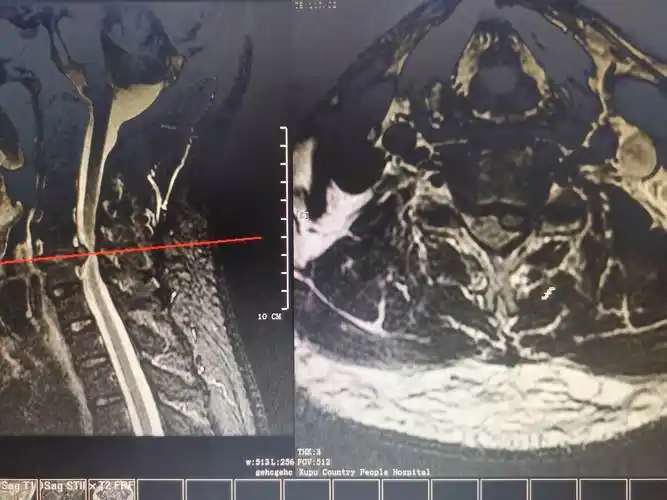

24岁颈椎骨质增生 - 聚图网